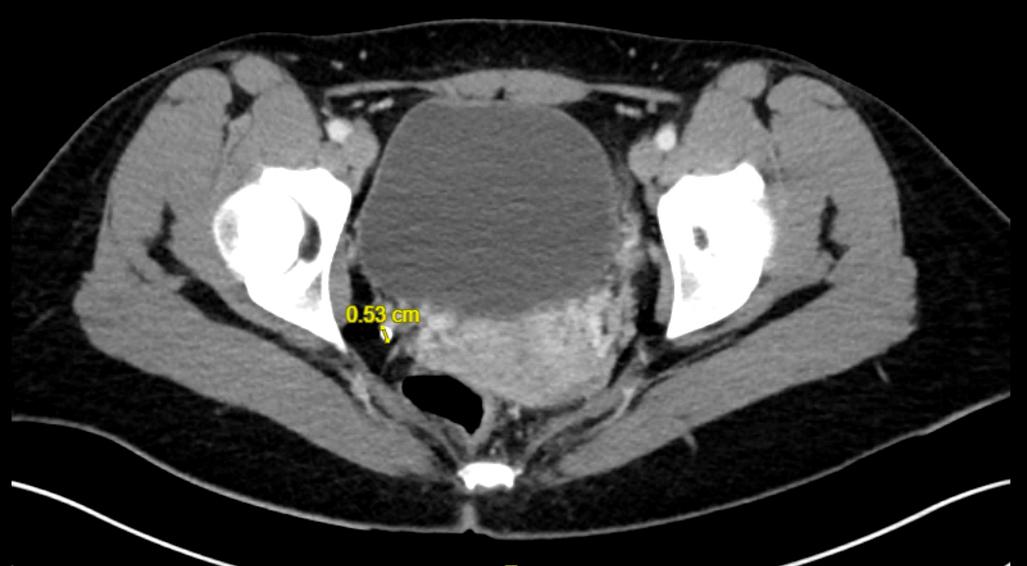

Théo Arber, La Revue du Praticien Scanner abdominopelvien non injecté. On y distingue un calcul pelvien droit de 0,53 cm.